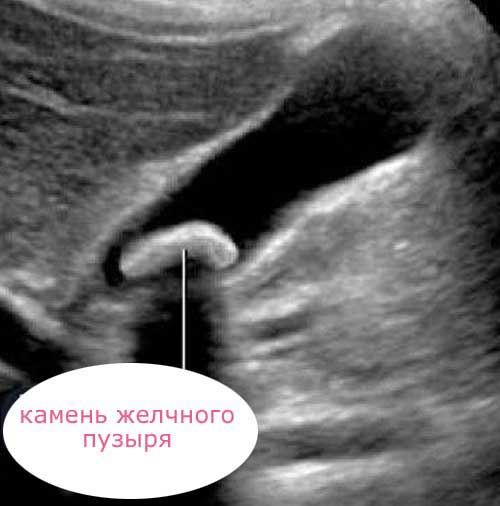

Желчный песок

Гомогенность или однородность содержимого пузыря может нарушить и присутствие желчного песка. Это мельчайшие (1-2-3 мм) плотные образования, которые представляют собой не что иное, как очень мелкие желчные камни.

Они, как правило, множественные и находятся на дне пузыря. Наиболее мелкие песчинки могут даже «плавать» в густой желчи. То есть, быть во взвешенном состоянии, что тоже нарушает гомогенность содержимого полости.

Желчные камни

Желчные камни — это очень плотные образования. На экране они практически белого цвета. Конечно, при обнаружении белых включений в полости желчного пузыря на фоне желчи о гомогенности его содержимого не может быть и речи.